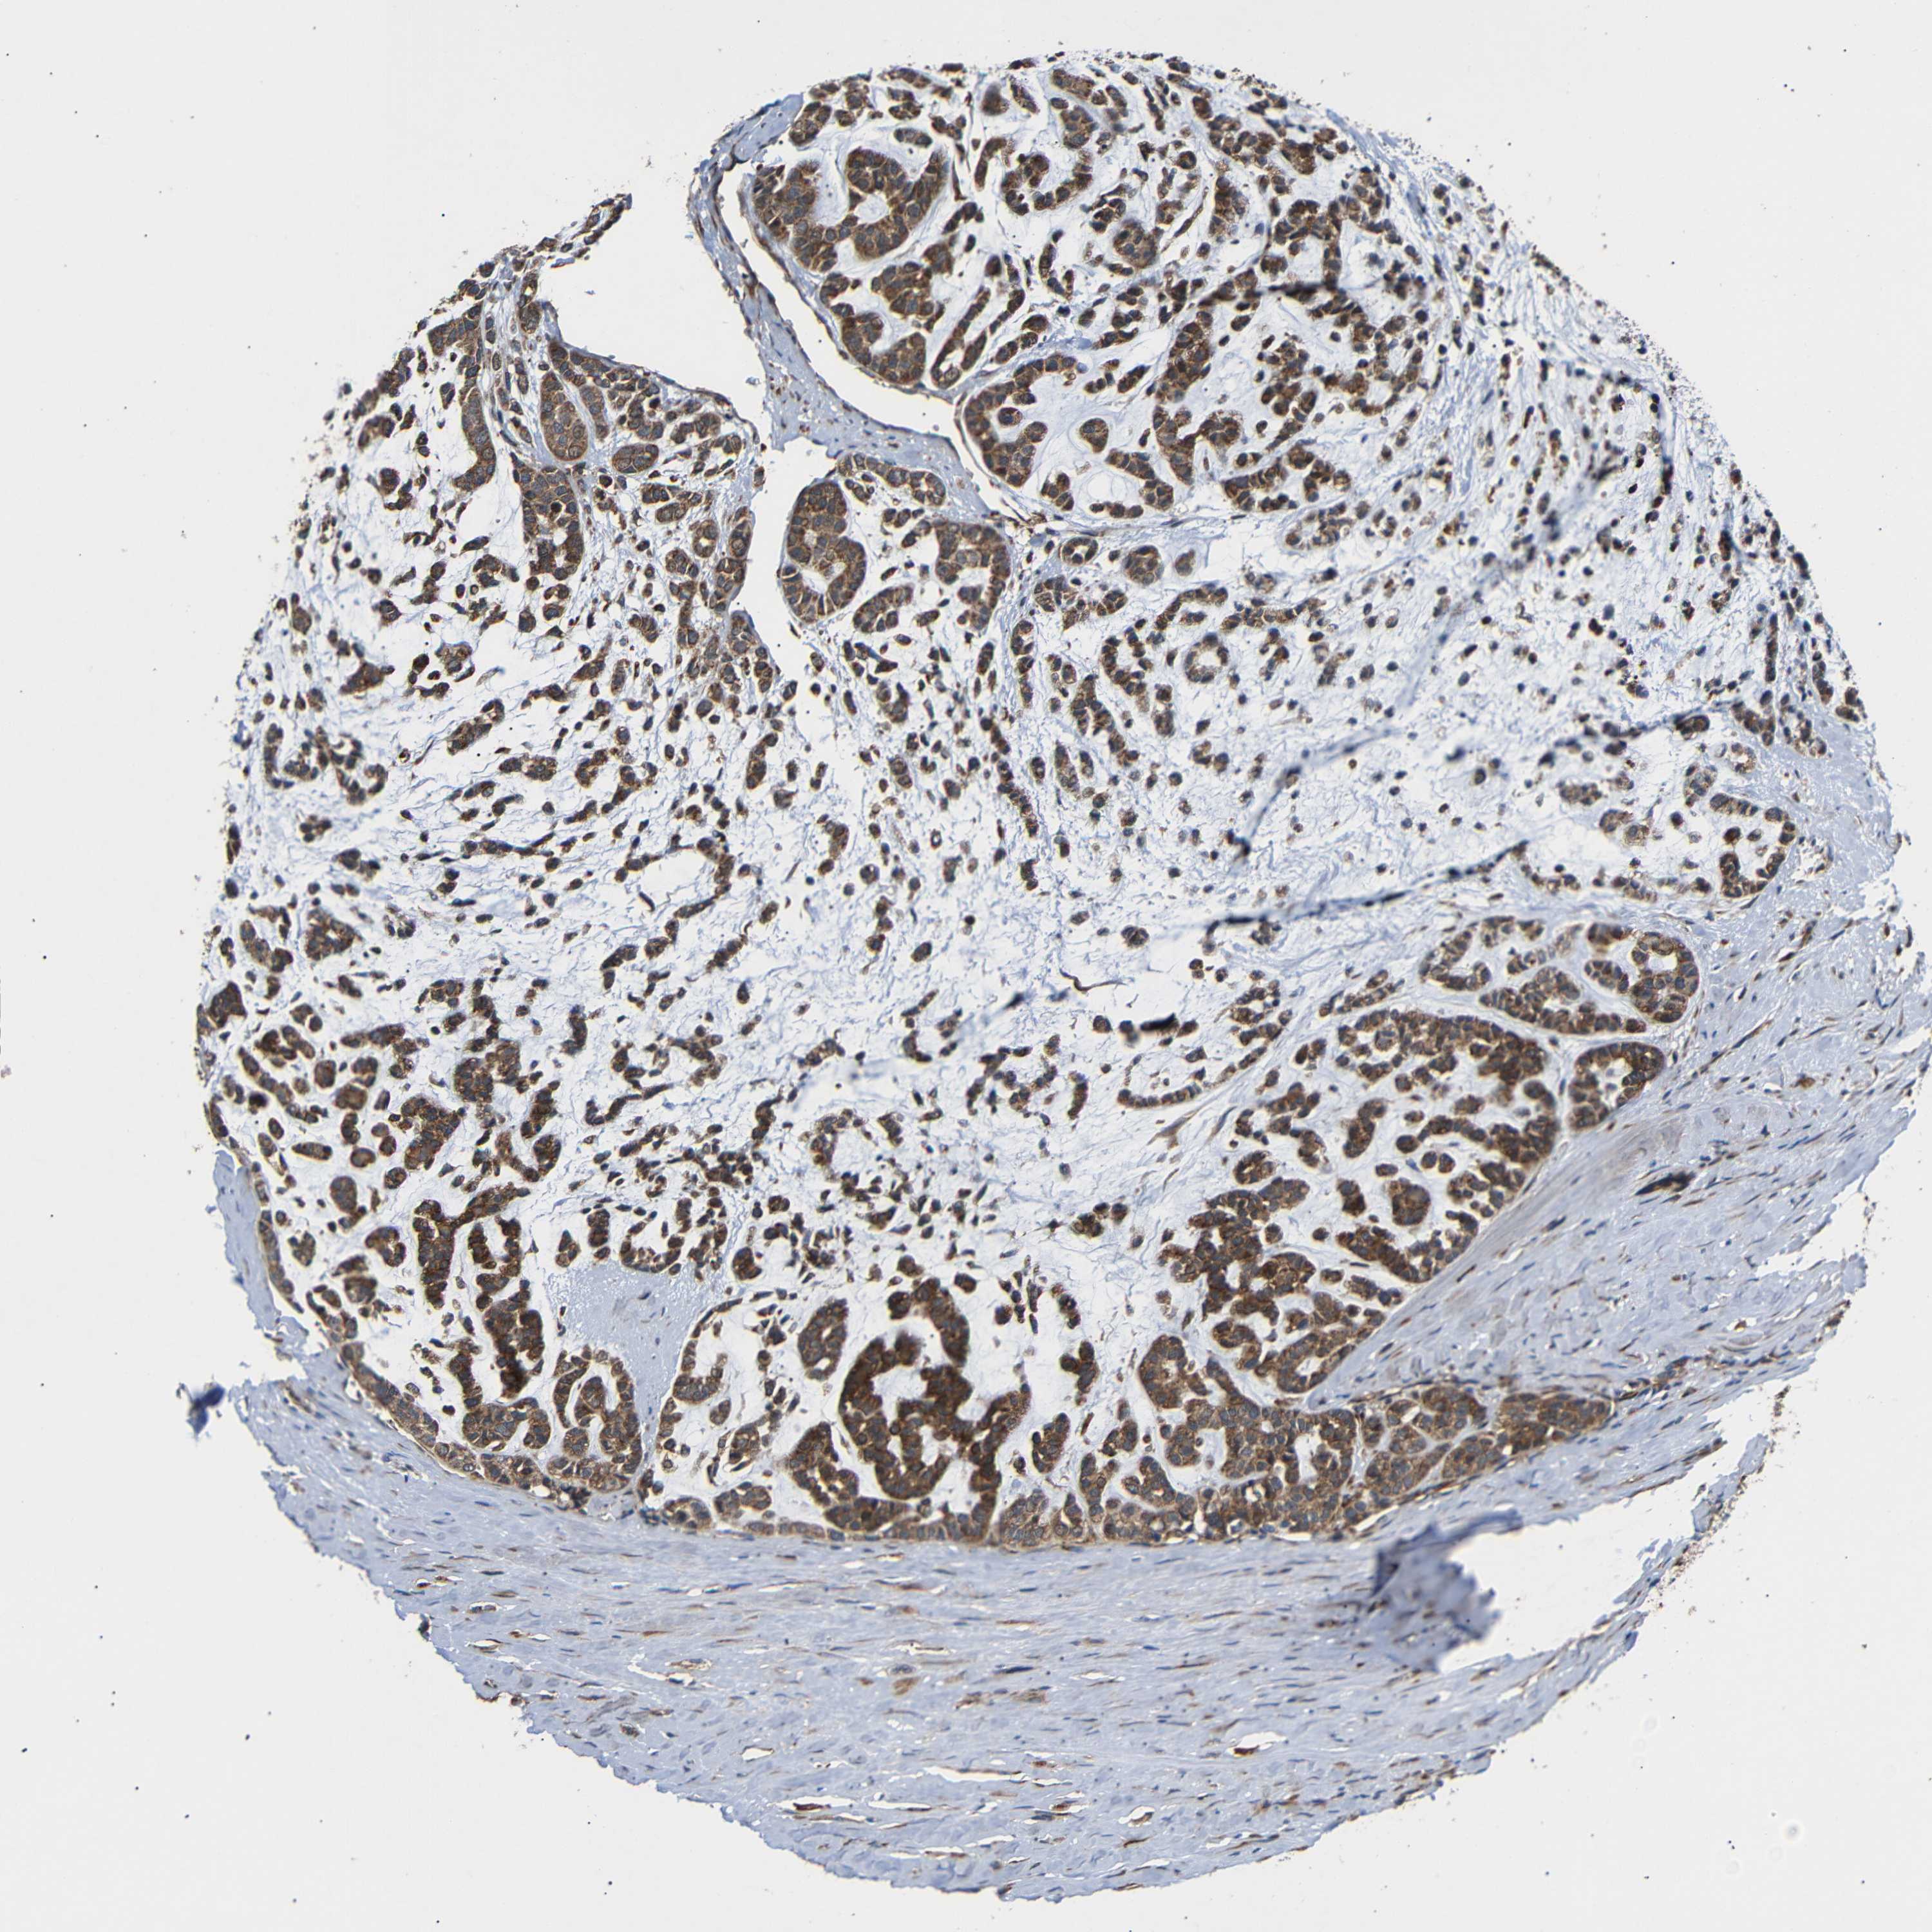

HEAD AND NECK CANCER - Protein expressioni

A mouse-over function shows sample information and annotation data. Click on an image to view it in a full screen mode. Samples can be filtered based on level of antibody staining by selecting one or several of the following categories: high, medium, low and not detected. The assay and annotation is described here.

Antibody stainingi

Antibody staining in the annotated cell types in the current human tissue is reported as not detected, low, medium, or high, based on conventional immunohistochemistry profiling in selected tissues. This score is based on the combination of the staining intensity and fraction of stained cells.

Each image is clickable and will lead to virtual microscopy that enables deeper exploration of all samples and also displays staining intensity scores, fraction scores and subcellular localization as well as patient and tissue information for each sample.

Antibody HPA014030

Staining

High

Medium

Low

Not detected

Intensity

Strong

Moderate

Weak

Negative

Quantity

>75%

75%-25%

<25%

None

Location

Nuclear

Cytoplasmic/membranous

Cytoplasmic/membranous,nuclear

Adenoma, NOS